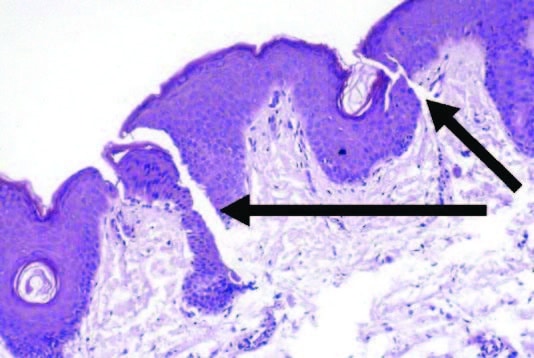

- Dieser Dermisbereich mit flacher DEJ ist die Zieltiefe für die Mikronadel. Siehe Pfeile, wo die Mikrokanäle gebildet werden

- Dieser Dermisbereich mit flacher DEJ ist die Zieltiefe für die Mikronadel. Siehe Pfeile, wo die Mikrokanäle gebildet werden